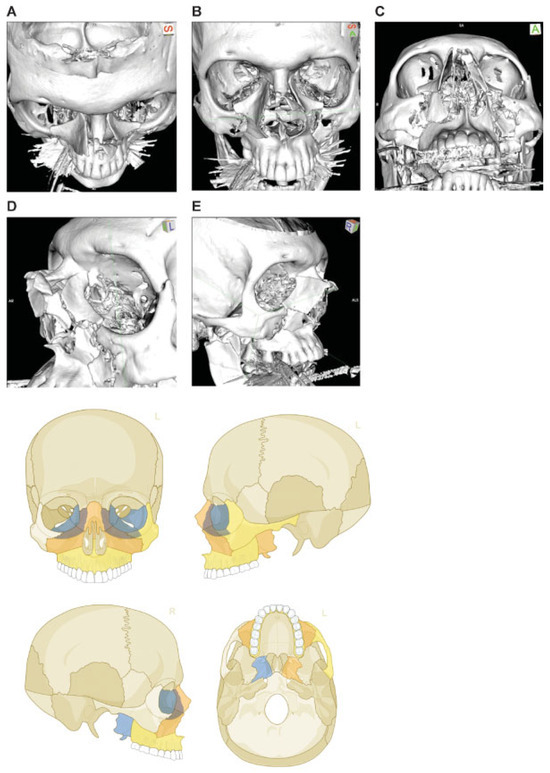

Figure 8.

Naso-orbito-ethmoidal fracture bilateral (Example 1). Imaging: Three-dimensional (3D) computed tomographic (CT) scans (A) upper frontal view, (B) frontal view, (C) lower frontal view, (D) oblique lateral view left, and (E) oblique lateral view right. Narrative description: Displacement and large-/medium-sized fragments in a bilateral Naso Orbito Ethmoid Fracture in combination with Le Fort I, II fracture, and left zygoma fracture. Note: Exclusive involvement of midfacial structures. (F) Level 3 Code: 92 I1i.L0.Pt.Oim.U1m.Omil.Pt1.L0.I1i.Z0i, Orbit (right)R(im).W1(im)2(im), Orbit (left)R(lim).W1(lim)2 (im). This case example CMTR-92-104 is made available electronically for viewing using the AOCOIAC software at www.aocmf.org/classification.